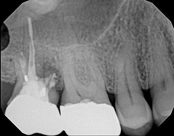

Upper molar failed root canal and apicoectomy:

Before

Immediately after

3-month follow-upThis person presented with one root that had failed from root canal treatment. The arrow in the picture, shows the infection as well as extra filling material that was pushed out of the root. An apical microsurgery was performed using the laser. The infection and excess material was cleaned out. Complete healing is visible 3 months after. The tooth was saved. This is a poor area for an implant.